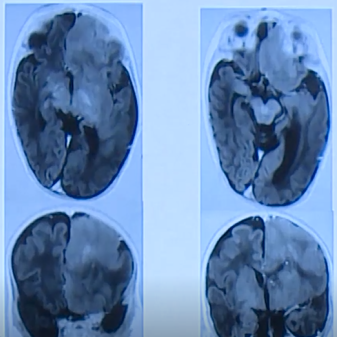

半侧巨脑综合征胎儿产前超声特征主要为:左右侧大脑半球不对称,病变侧明显大于对侧,并同侧侧脑室增宽;病变侧脑皮质较对侧肥厚,脑沟浅,大脑外侧裂增宽、变平直;脑中线向...